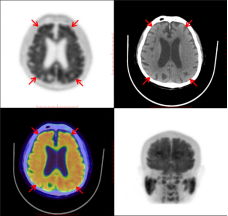

张大爷Aβ脑PET显像呈典型AD表现:皮质灰质放射性示踪剂摄取,从白质延伸至皮质带,致使灰白质分界模糊

刘阿姨脑多巴代谢显像呈典型PD表现:双侧尾状核及壳核多巴胺能神经末梢分布减低,以右侧壳核后部更显著